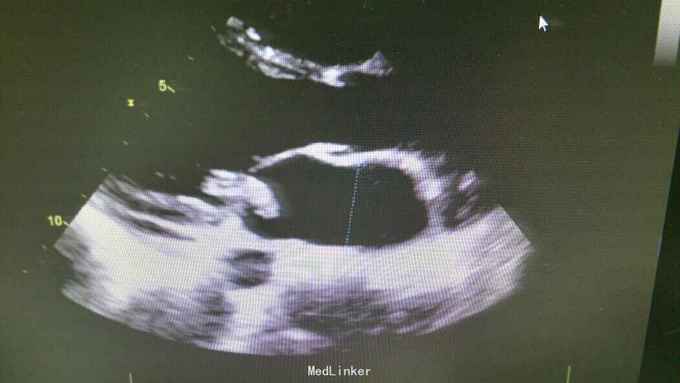

查体:T37.0℃,P110次/分,R26次/分,BP96/68mmHg。发育正常,营养一般,神志清楚,对答切题,轮椅送入院,查体合作。全身皮肤粘膜无黄染、皮疹,出血点及淤斑,未见Janeway结节,未见Osler结节及甲床下出血,无发绀,未见杵状指、趾,周围血管征阴性。浅表淋巴结未及肿大。巩膜无黄染,结膜无出血。口腔黏膜光滑,咽不红,扁桃体部大,颈静脉无明显搏动,未见怒张,气管居中,胸背部听诊双下肺闻及细小湿啰音。心前区无隆起或抬举性搏动,心尖搏动以左侧第六肋间锁骨中线外1.5cm处明显,未扪及震颤,心界向两侧稍扩大,心率110次/分,律齐,心音有力,P2稍亢进,无固定分裂,心尖区闻及3-4/6级收缩期吹风样杂音,向心底部传导,未闻及舒张期杂音,未闻及心包摩擦音。腹平软,无压痛及反跳痛,肝脾肋下未及,肠鸣音正常。脊柱、四肢关节无异常,活动好,双下肢无浮肿。 2015年10月30日汕头市中心医院心彩超:二尖瓣及瓣下腱索及左室心内膜多发赘生物形成,二尖瓣前瓣穿孔,重度二尖瓣关闭不全,左心系统扩大,心肌舒张功能下降,收缩功能正常,感染性细菌性心内膜炎,微量心包积液。 2015-11-1血常规:中性粒细胞比例 0.949,血红蛋白浓度 117.000(g/L),中性粒细胞计数 18.360(10E9/L),白细胞计数 19.350(10E9/L),血小板计数 343.000(10E9/L),红细胞计数 4.350(10E12/L)。 B超:双侧颈动脉血流通畅,双侧椎动脉未见狭窄。双侧甲状腺不大、未见占位,血供尚丰富。双侧颈部淋巴结声像,双侧乳腺未见明显占位,超声BI-RADS分类1类,双侧腋窝淋巴结声像。双肾未见结石与积水,双肾动脉主干血流连续,膀胱未见明显结石,双侧肾上腺区未见明显占位。肝脾胰不大,未见占位,胆囊未见明显结石,子宫及双侧附件区未见明显占位,宫后积液(少量)。 胸部CT:1、两下肺叶后基底段局部节段性肺炎。右肺中叶少许纤维化病灶。2、双侧胸腔少量积液。 胸片:考虑双肺炎症。 心电图:心率84次/分,窦性心律,肢体导联低电压,前间壁R波上升不良。 心彩超:1、考虑感染性心内膜炎:二尖瓣赘生物形成,伴中重度二尖瓣反流。中度三尖瓣反流。3、左房内径增大,肺动脉增宽。 头颅MR:左侧额叶、左侧放射冠侧脑室前角旁脑白质异常信号,考虑感染性病变及缺血灶可能性大。 2015-11-2查血常规:中性粒细胞比例 0.840,血红蛋白浓度 103.000(g/L),中性粒细胞计数 14.730(10E9/L),白细胞计数 17.540(10E9/L),红细胞计数 3.890(10E12/L),血小板计数 353.000(10E9/L)。 10月31日左上肢、右上肢、下肢血培养均提示:草绿色链球菌,对万古霉素敏感。 2015-11-6肾功能:肌酐 130.000(umol/L),尿素氮 5.250(mmol/L),二氧化碳结合力 30.500(mmol/L),电解质:钠 138.000(mmol/L),氯 96.000(mmol/L),钾 3.500(mmol/L),钙 2.310(mmol/L),肝功能:白、球蛋白比例 1.300,未结合胆红素 10.500(umol/L),总胆红素 17.900(umol/L),丙氨酸氨基转移酶 31.000(U/L),总蛋白 75.000(g/L),球蛋白 32.000(g/L),白蛋白 43.000(g/L),结合胆红素 7.400(umol/L),门冬氨酸氨基转移酶 31.000(U/L),脑钠肽:191.400(pg/ml)。 24小时心电图:窦性心律,房性早搏,部分成对,短阵房速,多源室早,部分成对,部分呈三联律,短阵室速。

根据患者病史、查体、辅助检查可明确术前诊断:1、亚急性感染性心内膜炎:二尖瓣赘生物形成,二尖瓣关闭不全(中-重度),三尖瓣关闭不全(中度),心功能Ⅱ-Ⅲ级。2、肾功能不全。3、贫血。予选择敏感抗生素抗感染治疗,先用万古霉素1g q12h+阿米卡星0.3 q12h,抗感染治疗,后查肌酐升高,肌酐 145.000(umol/L),肾功能受损,考虑与万古霉素有关,请临床药师会诊建议调整抗生素,11-8改头孢曲松1g q12h抗感染。另积极强心、利尿、控制心率、营养心肌、提高免疫力、输血等治疗,患者仍间有高热、畏寒,存在肾功能损害、贫血,手术时机不能拖延。2015-11-12全麻体外循环下行左心赘生物清除、二尖瓣置换、三尖瓣成形、卵圆孔未闭修补术。 手术记录: 平卧位,麻醉诱导插管,左桡动脉穿刺置管测血压,右颈内静脉穿刺置管测中心静脉压及输液,留置导尿管,安尔碘消毒皮肤,常规铺巾,贴皮肤保护膜。正中切口,纵锯胸骨进胸,正中切开心包,术中探查:少-中量淡黄色心包积液,右心房、右心室明显增大,主动脉:肺动脉=22:28(mm),肺动脉扪诊张力较高,主动脉根部无震颤。常规主动脉、上、下腔静脉套带,缝合荷包,上腔静脉荷包用4-0prolene线缝在上腔静脉根部。肝素化(3mg/kg),依次插主动脉管(20号)、上腔管(26号金属直角管)、下腔管(32号),转机并行循环,右上肺静脉插左心引流管,主动脉根部插灌注针。阻断上、下腔静脉,阻断主动脉,顺灌4:1含血停跳液300ml,心表冰泥降温保护心肌,心脏停跳,纵形切开右房见卵圆孔未闭,切开房间隔,探查见二尖瓣败坏严重,前瓣靠瓣沿有一较大赘生物,瓣下腱索上也有芝麻粒大小赘生物,后瓣靠前交界瓣叶上右大小不等赘生物,腱索挛缩,将瓣叶及赘生物粘在左室后壁,瓣口关闭不全,左房后壁靠瓣环前交界附近有散在的米粒或芝麻大小赘生物,无附壁血栓。切除病变瓣膜及腱索,仔细清除左心室、瓣环及左房后壁赘生物,高效碘消毒左心腔,大量冰生理盐水反复冲洗左心室,测量瓣环可容27号,全周带垫片褥式缝合14针,再次冲洗左心室,用carbomedics 27号瓣,上瓣打结,检查瓣膜固定满意,瓣叶开闭正常,将左心引流管通过瓣口置入左心室内,用4-0prolene线封上下角后连续往返缝合房间隔切口,修补未闭卵圆孔。探查三尖瓣环扩大达3横指多,用3-0proline线带垫片缝缩三尖瓣后瓣环(半个devage成形),做三尖瓣成形至能通过约2个横指,主动脉灌注针及左心管排气,开放主动脉阻断钳,心脏自动复跳,为结性心率,心率慢,约50-60次/分。用4-0prolene线关闭右心房切口。辅助循环后转为窦性心律。复温及并行循环辅助后血流动力学稳定停机,依次拔出左心管、下、上腔管,主动脉根部注射鱼精蛋白,拔出主动脉管,检查心脏各切口并止血,心脏各切口覆盖艾薇停(1包)、胶原蛋白海绵(2包),3-0滑线连续缝合心包,电烙骨腊止血,留置心包及纵膈引流管,5根钢丝对合胸骨,逐层缝合关胸,术毕。 术后继续孢曲松1.5g q12h+庆大霉素4万U q8h抗感染,另积极强心、利尿、控制心率、营养心肌、抗凝、提高免疫力、补充营养等治疗,患者无发热、寒战,全身状况好转,但出现反复双侧胸腔积液及心包积液,予心包穿刺引流及胸腔闭式引流。目前患者在平稳恢复中,治愈出院。